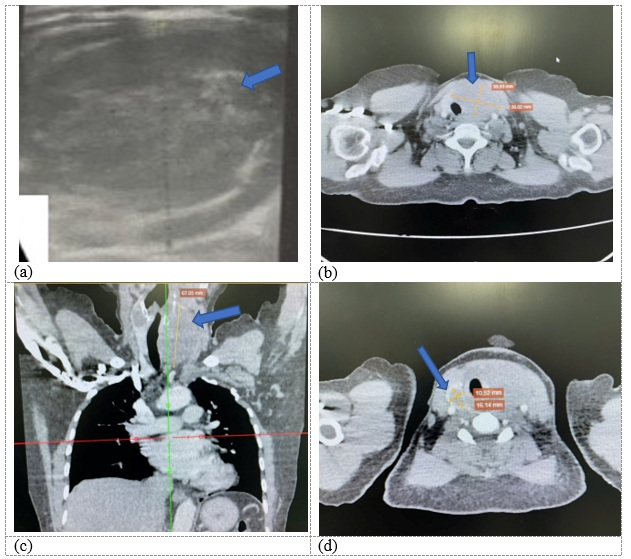

Laboratory evaluation revealed a red-blood-cell count of 5.71 × 10¹²/L, haemoglobin 14.6 g/dL, platelet count 327 × 10⁹/L, and white-blood-cell count 9.9 × 10⁹/L with neutrophils 59 %. Serum electrolytes and liver enzymes were within normal limits (Na⁺ 139 mmol/L; K⁺ 3.64 mmol/L; Cl⁻ 100.2 mmol/L; AST 20.5 U/L; ALT 20.3 U/L). Thyroid function tests showed TSH 2.15 mIU/mL, T₃ 160.3 ng/dL, free T₄ 1.4 ng/dL; thyroid-specific antibodies were elevated (TSH-receptor antibodies 2.75 IU/L; anti-thyroid peroxidase > 600 IU/mL; anti-thyroglobulin 82.86 U/mL). Calcitonin was 0.51 pmol/L and thyroglobulin 1146 ng/mL. Thyroid ultrasonography demonstrated a 38 × 16 mm poorly defined hypoechoic lesion occupying the left lobe (Figure 1A). Contrast-enhanced neck CT identified two intrathyroidal lesions with well-defined margins and poor enhancement (Figure 1B-C). The imaging appearance was suggestive of chronic thyroiditis consistent with Hashimoto thyroiditis.

Pre-operative imaging.A) Thyroid ultrasound (transverse view) shows a poorly defined, hypoechoic mass (38 x 16 mm) in the left lobe. B-D) Contrast-enhanced computed tomography (CT) scans of the neck. B, C) A large, well-defined nodule (55 x 38 mm) in the left thyroid lobe with poor contrast enhancement, causing mild compression and displacement of the trachea and esophagus. D) A smaller nodule (14 x 17 mm) in the right thyroid lobe.